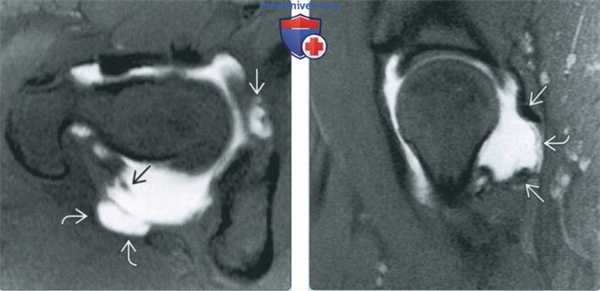

(Справа) МР-артрография в режиме Т1ВИ FS, косоаксиальный срез, этот же пациент: выявляется отслоение суставной губы ниже восстановленного участка. Область, подвергшаяся остеохондропластике, ничем не примечательна. (Слева) МР-артрография в режиме Т2ВИ FS, коронарный срез, этот же пациент: суставная капсула растянута, восстановленный участок суставной губы имеет неровный контур и содержит зону, интенсивность сигнала которой соответствует интенсивности сигнала от жидкости. Для дифференциации грануляционной ткани и контрастного препарата в разрыве суставной губы, необходим режим Т1.

(Справа) МР-артрография в режиме PD FS, сагиттальный срез, этот же пациент: отмечается неровный контур восстановленного участка суставной губы, а также локальное истончение суставного хряща. Область, подвергшаяся остеохондропластике, ничем не примечательна.